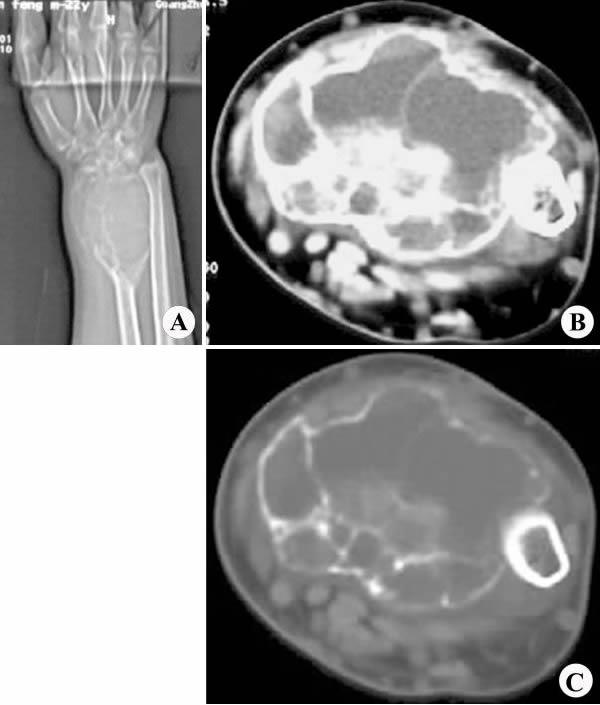

右桡骨远端骨巨细胞瘤

【影像表现】:CT定位像(A)示右桡骨远端皂泡状膨胀性骨质破坏区,边界清楚;横断面平扫软组织窗(B)、骨窗(C)示破坏区形态不规则,呈软组织密度,内见高密度骨性间隔。

【影像诊断】:右桡骨远端骨巨细胞瘤。